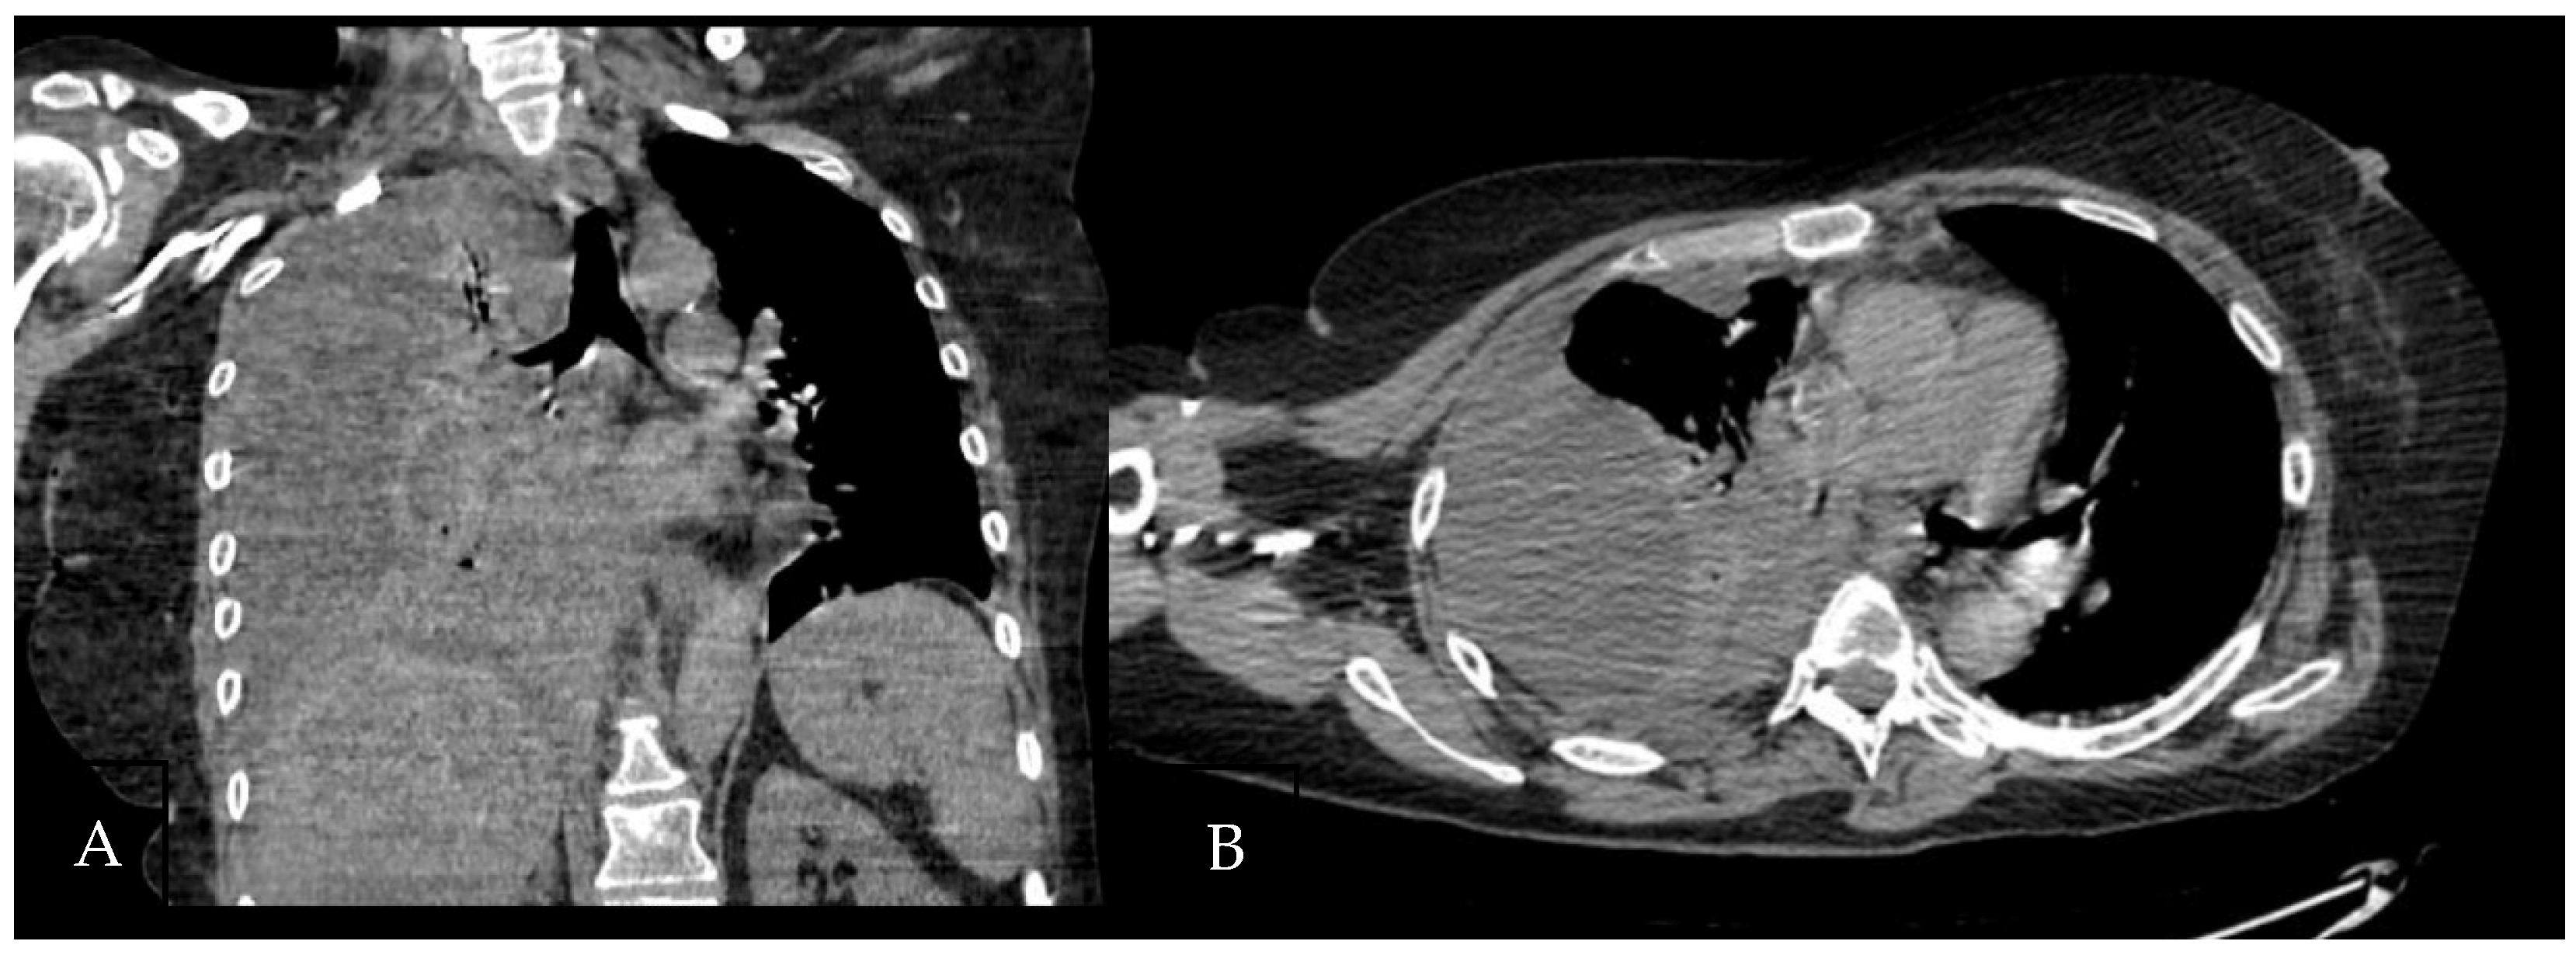

A 60-year-old Caucasian man was admitted to our hospital with a history of worsening pain at the base of the right hemithorax and feeling generally unwell for over one month. The patient’s past medical history included coronary heart disease, with a percutaneous coronary intervention in 2014. He smoked a half-pack of cigarettes per day for 40 years and had no history of respiratory disease. The CT chest scan showed a fluid collection in the medium–lower parts of the right hemithorax with thickened walls and contrast enhancement (Figure 5). This collection appeared in continuity with further smaller fluid collections with thickened walls, contrast enhancement, and confluence and caused the complete atelectasis of the middle and lower lobes and the partial atelectasis of the upper lobe, as well as middle and inferior lobar bronchus occlusion.

Figure 5. Chest CT scan of the mediastinal window in the coronal (A) and axial (B) plane, showing fluid collection in the medium–lower parts of the right hemithorax (maximum axial dimeters of 19 × 13 cm; craniocaudal extension of 16 cm) with thickened walls and contrast enhancement. There is also a complete atelectasis of middle and lower lobes and partial atelectasis of the upper lobe.